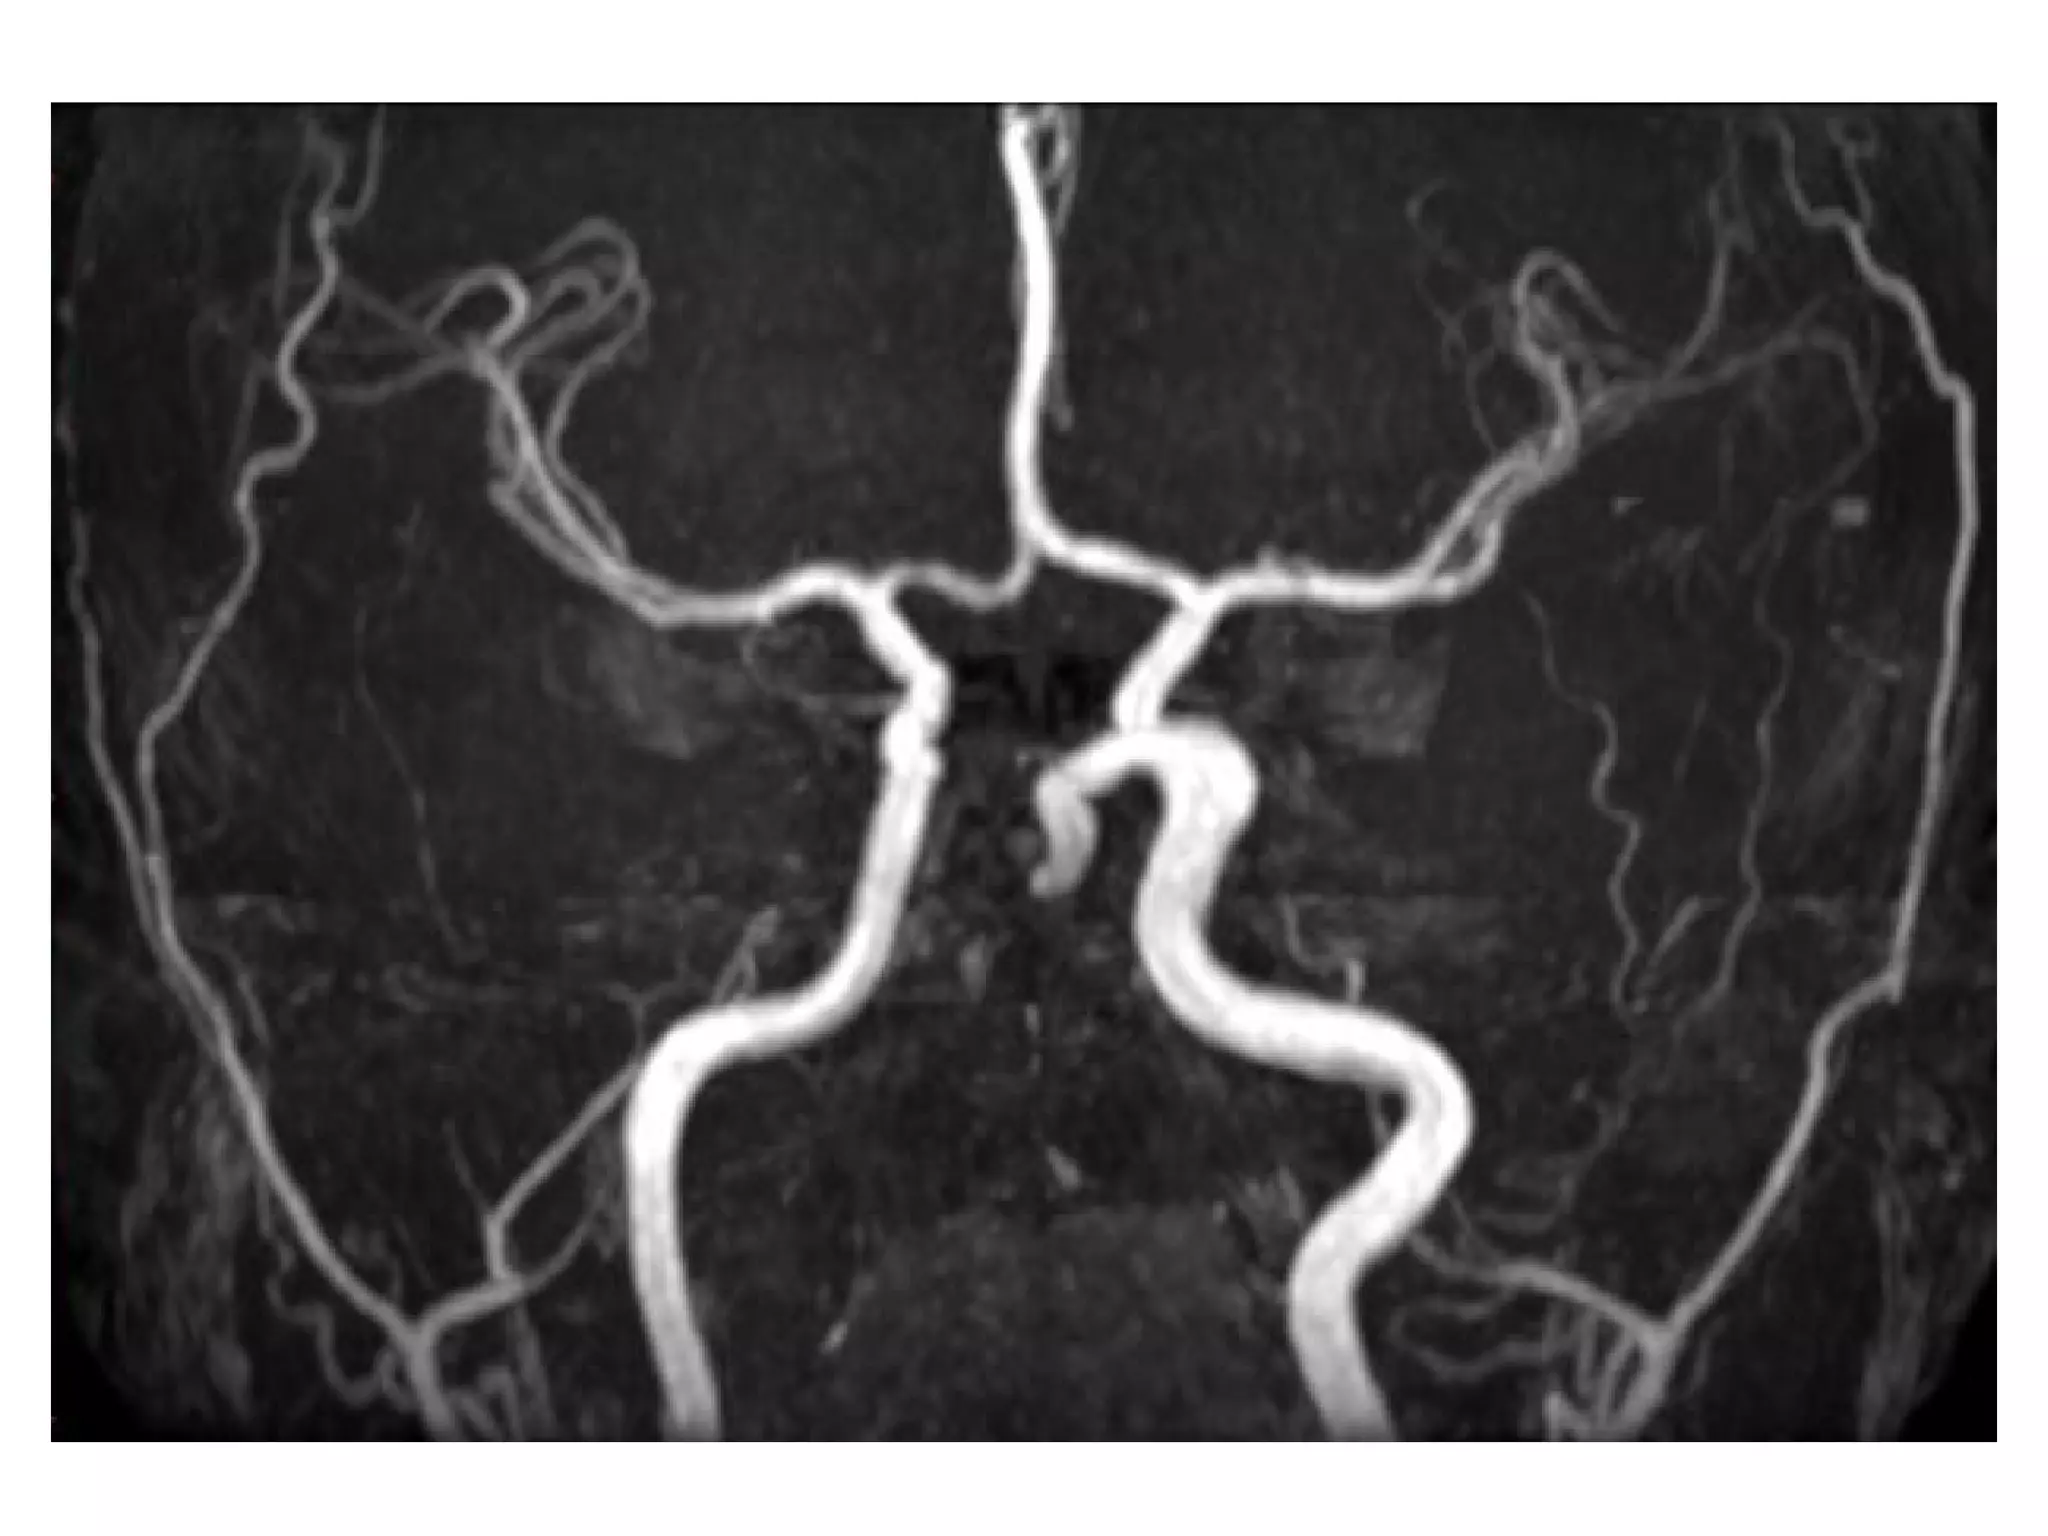

Right MCA occlusion , 3D TOF MRA MIP shows absent flow-related

enhancement in the right MCA from embolic occlusion